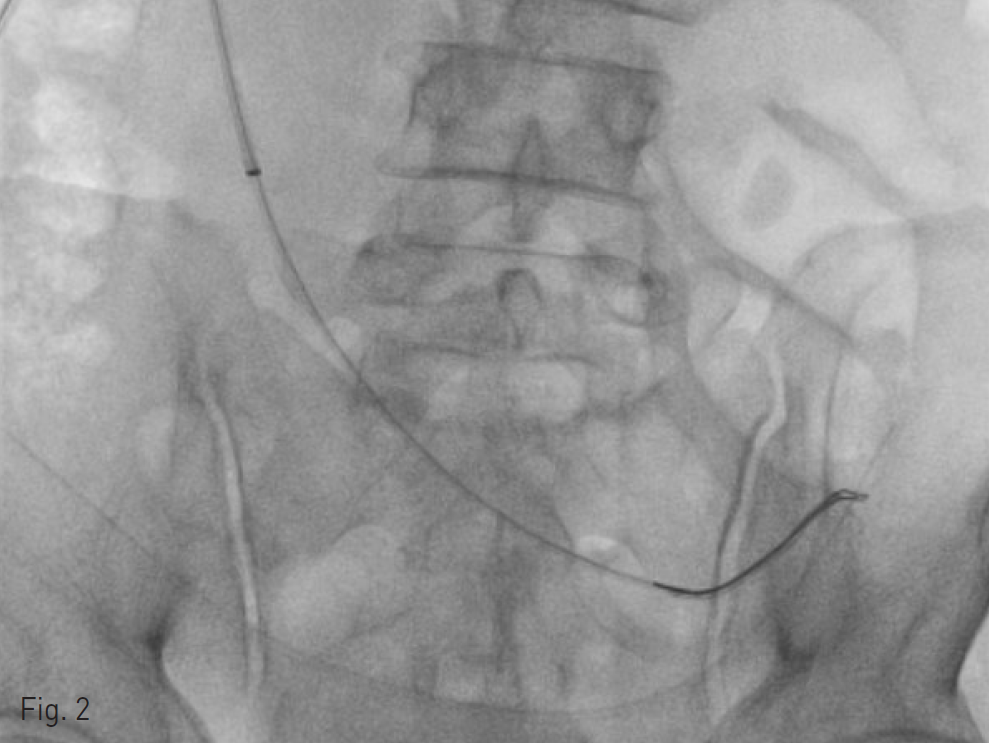

Fig. 1. Jackson Pratt drain tube tip in the pelvic cavity.